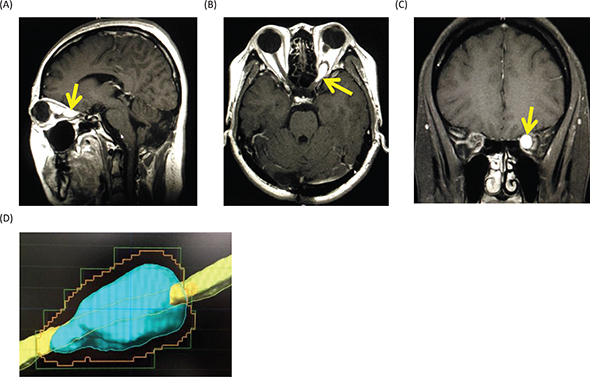

Magnetic resonance imaging (MRI) of the head showed a Gd-enhanced well-circumscribed mass on the left retrobulbar optic nerve in the orbital, and three-dimensional MRI showed the tumor enveloped the left optic nerve (Figure 4).

Fig 4

Figure 4. Magnetic resonance images before radiosurgery. (A) Gadolinium (Gd)-enhanced T1-weighted image, sagittal. (B) Gd-enhanced T1-weighted image, axial. (C) Gd-enhanced T1-weighted image, coronal. Yellow arrows show the tumor. (D) Three-dimensional planning MRI for radiosurgery. The light blue color indicates the tumor enveloping the optic nerve.

The differential diagnoses for the tumor include optic glioma, optic sheath meningioma, optic nerve schwannoma and optic nerve hemangioblastoma. Among them, since the patient is a VHL patient, the most probable diagnosis was thought to be an optic nerve hemangioblastoma. Therefore, we made a decision to treat the tumor with stereotactic radiosurgery. At Shonan Fujisawa Tokushukai Hospital, the stereotactic radiosurgery was prescribed with the dose being 39 Gy/13 fractions using Novalis. The planning target volume was set at 0.7 mL, and D95 (95% of standard irradiation volume) was set at 35 Gy/13 fractions. The patient completely lost her vision after the radiosurgery. Eighteen months after the radiosurgery, the tumor volume slightly decreased (Figure 5), but her vision has been still lost. The consent to publish the case has been given by the patient.